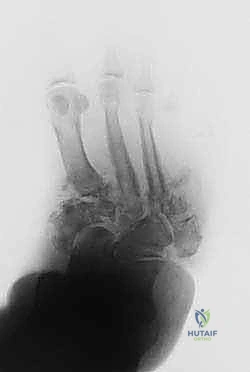

- المرحلة الأولى (مرحلة التطور والتفتت): تدمير حاد. تظهر الأشعة تفتت العظام، خلع المفاصل، وتكون شظايا عظمية. القدم تكون حمراء، ساخنة، ومتورمة بشدة.

- إدخال الأسلاك: يتم تمرير أسلاك معدنية رفيعة جداً وقوية (K-wires) ومسامير نصفية (Half-pins) عبر العظام في الساق والقدم بأماكن استراتيجية محددة مسبقاً بدقة لتجنب الأعصاب والأوعية الدموية، وذلك تحت توجيه الأشعة السينية المباشرة (C-arm) في غرفة العمليات.

- تجميع الإطار: يتم توصيل هذه الأسلاك بحلقات خارجية معدنية أو كربونية تحيط بالساق والقدم (إطار إليزاروف). يتم تثبيت هذه الحلقات معاً بواسطة دعامات قابلة للتعديل.